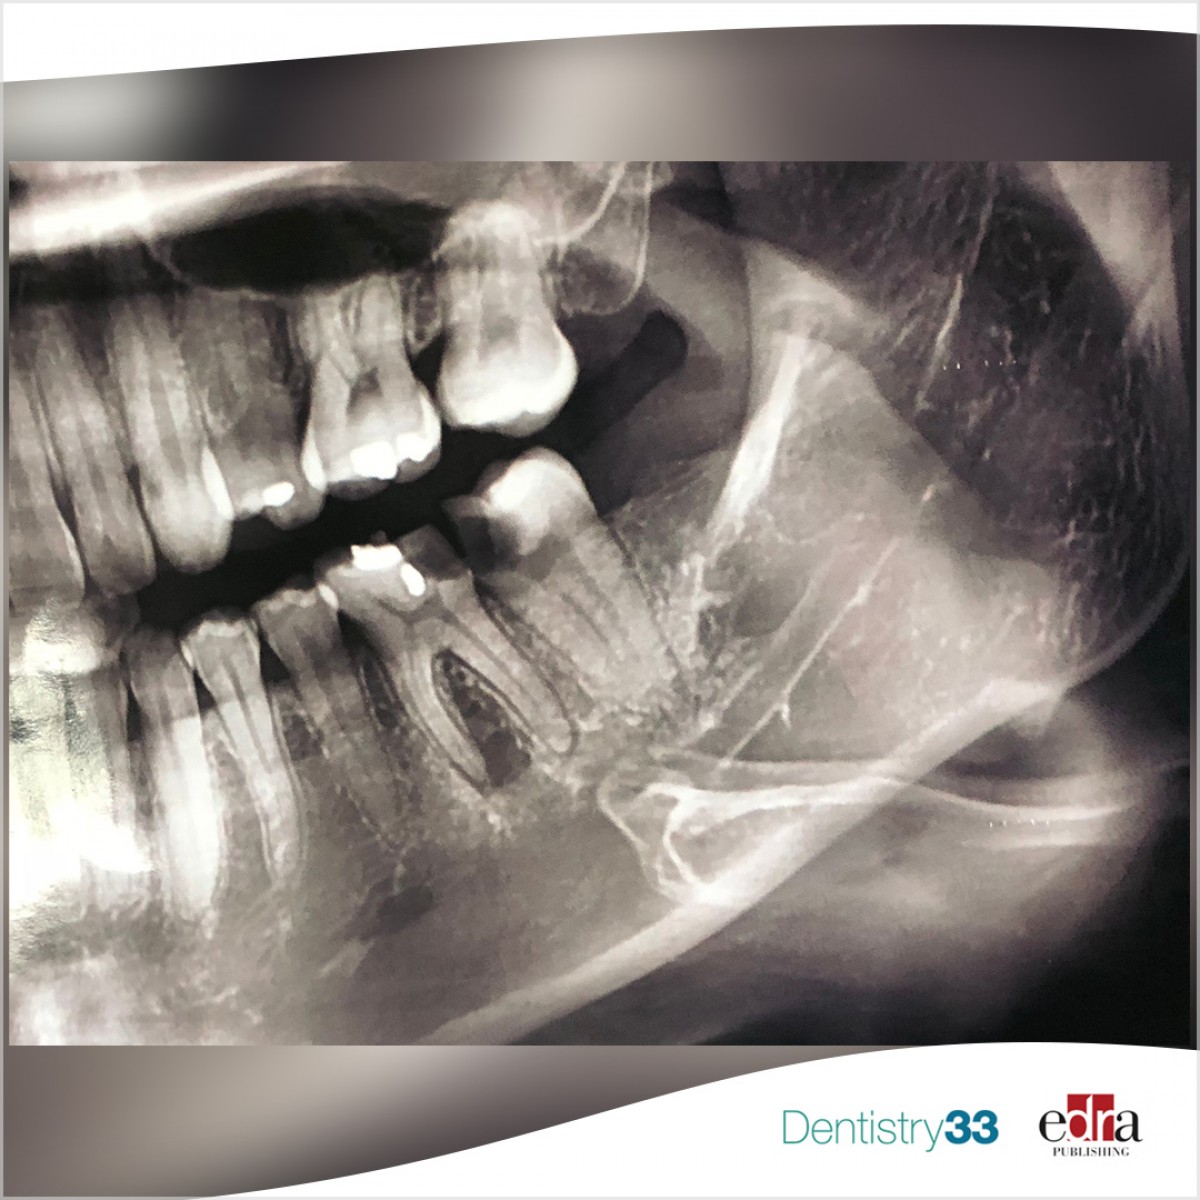

Direct or indirect composite for restoring permanent first molars affected by molar incisor hypomineralization

This study was undertaken to compare direct composite resin restorations (DCRR) and indirect composite resin restorations (ICRR) for treating permanent first molars affected by MIH in terms of clinical performance.

This was a controlled, randomized, clinical split-mouth study. The studied sample consisted of 40 asymptomatic first permanent hypomineralized mandibular molars in 20 children aged between 7–11 years, these cases were divided randomly into two groups: Group 1 (experimental): 20 first permanent mandibular molars were restored with ICRR, and Group 2 (control): 20 first permanent mandibular molars that were restored with DCRR.

The clinical success rate was 90% in the ICRR group versus 85% in the DCRR group after 12 months of follow-up without statistically significant differences (P = 0.218). Children were significantly more satisfied (P = 0.0351) with ICRR than DCRR.

Both DCRR and ICRR can be considered effective restorations with acceptable clinical performance in the restoration of hypomineralized first permanent molars with an advantage of ICRR in terms of child acceptance of the restoration application technique.